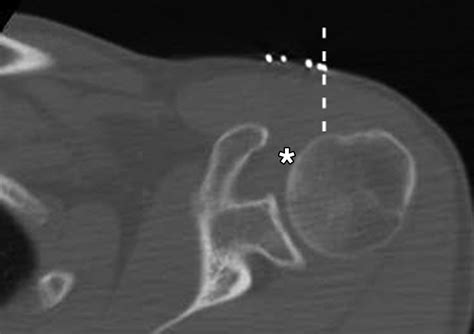

Accurately diagnosing conditions affecting the rotator cuff interval requires a combination of physical examination and advanced imaging. Physicians typically begin with clinical tests to isolate the function of the biceps tendon and the rotator cuff muscles. However, because the interval is deep, imaging is vital for a definitive diagnosis.

Magnetic Resonance Imaging (MRI) The gold standard for visualizing soft tissue, ligamentous thickening, and interval tears.

Magnetic Resonance Arthrography (MRA) Provides enhanced detail by injecting contrast into the joint, ideal for detecting minor labral or interval ligament tears.